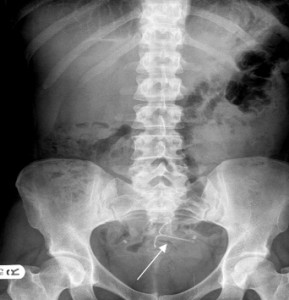

Upon further investigation, it was discovered that Sloan’s IUD had migrated outside of her uterus and was now located in her abdominal cavity. On December 16, 2014, many months after the migration of the Mirena was discovered, Sloan underwent a laparoscopic procedure to remove the IUD. A hysterectomy was also performed at that time, allegedly due to the injuries incurred by the device.

The FDA has received more than 45,000 adverse reports involving the Mirena IUD, filed by patients who have suffered serious complications from the device. Spontaneous migration of the IUD, which Sloan experienced nearly four years after the initial implantation, has caused perforation of the uterus, unintended pregnancy and damage to abdominal organs in numerous patients.